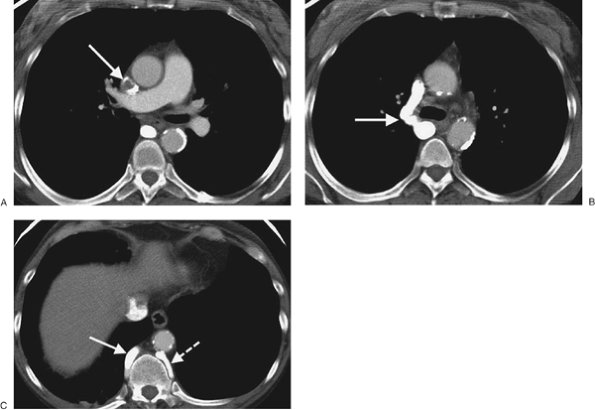

FIGURE 17-22. Superior vena cava thrombus. A: CT of a 47-year-old woman on hemodialysis shows nearly complete occlusion of the superior vena cava with thrombus (arrow). B: CT at a more inferior level shows collateralization of blood flow through an enlarged right azygos vein (arrow). C: CT at a level inferior to (B) shows enlargement of the azygos (solid arrow) and hemiazygos (dashed arrow) veins.